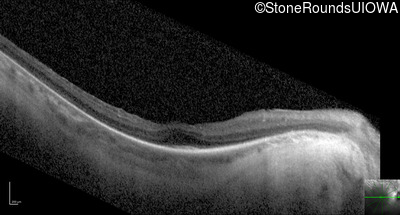

Optical Coherence Tomography - Right - 20/50 -2

Exemplar / OCT Stack

OCT Stack